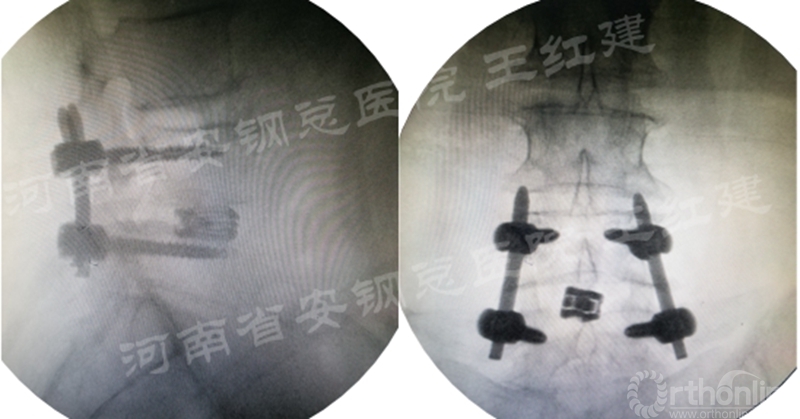

四、经皮螺钉技术固定

在固定的步骤可以先期进行经皮螺钉置入,再进行融合器的置入,进而实现充分固定。

椎弓根植入加压固定

单边椎弓根植入加压固定

双侧椎弓根植入加压固定

手术步骤:先期经皮螺钉置入、再进行融合器的置入